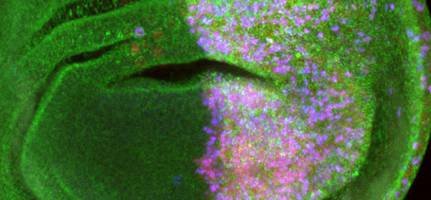

Berner Krebsforschende bremsen tödliche Blutkrankheiten

Viele Leukämie-ähnliche Blutkrankheiten sind bislang unheilbar. Forschende der Universität Bern verlangsamten nun erfolgreich das Fortschreiten der Krankheiten, indem sie einen bestimmten Botenstoff blockierten. Myeloproliferative Neoplasien (MPN) sind eine Gruppe oft tödlich verlaufender, chronischer Bluterkrankungen.